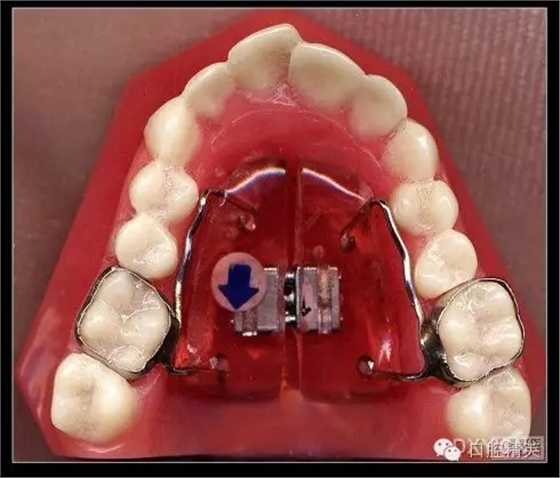

三、擴弓器

很多牙列不齊常伴隨牙弓過窄,所以擴弓器是正畸醫(yī)生的好伙伴,它可以以多種形態(tài)和您見面。